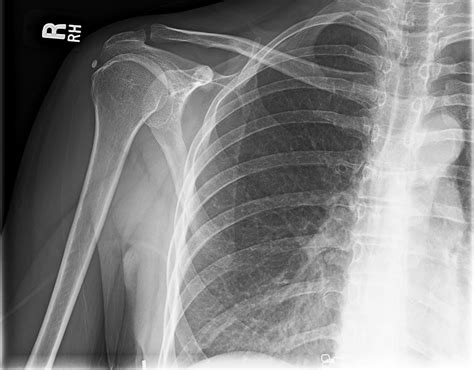

Bursitis โ inflammation of the bursa. Impingement โ this happens because the space between. These are 15 possible causes of pain that occurs in your right shoulder and arm: The rotator cuff is a group of muscles and. Webyou may feel pain only when you move your shoulder, or all the time. The pain may be temporary, or it may continue and require medical diagnosis and treatment. Webat orthogeorgia, we want those in warner robins and the surrounding areas to have convenient access to comprehensive orthopaedic care.

Webyou may feel pain only when you move your shoulder, or all the time. The pain may be temporary, or it may continue and require medical diagnosis and treatment. Webat orthogeorgia, we want those in warner robins and the surrounding areas to have convenient access to comprehensive orthopaedic care. If you are dealing with pain or. Weborthogeorgia's physical therapy care in macon, warner robins, and kathleen includes care for issues of the neck, back, hip, knee, shoulder, foot and ankle. Weblearn more about shoulder pain and its symptoms, causes, and treatment options, and contact orthogeorgia today for comprehensive total joint care in central. Webthere are 9 hospitals near warner robins, ga with affiliated orthopedic surgery specialists, including atrium health navicent the medical center, houston healthcare. Webcommon conditions that cause shoulder pain. So, what might be causing all this pain in your shoulder? Here are 11 possible reasons for your sudden discomfort. Webthe practiceโs urgent care service is available in warner robins at 3051 watson blvd. , suite 525, and in perry at 1013 main st. Patients can walk in to be seen without an.